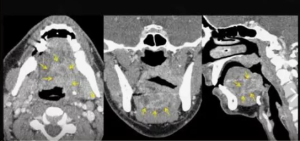

На рис. 1 и 2 иллюстрируется инвазия плоскоклеточной карциномы в скелетные и собственные мышцы языка при МРТ и МСКТ с контрастированием пациентки А., 57 лет, и пациента Х., 61 лет, в двух ортогональных плоскостях: аксиальной и корональной.

Оценка глубины инвазии проводилась с использованием МРТ и МСКТ посредством измерения расстояния от условной линии, проведенной перпендикулярно между точками перехода опухолевой и здоровой ткани, до наиболее глубокой точки опухолевого процесса. Все измерения выполнялись с помощью МСКТ и МРТ с контрастированием в аксиальных и корональных проекциях.

Основные диагностические критерии включали патологическое увеличение тканей, инфильтративные изменения мышечных структур, неоднородность опухолевой массы вследствие некротических изменений, а также оценку глубины инвазии.